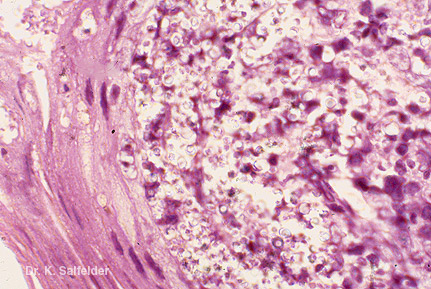

Abb. 8,36: Sporotrichose

Hautlaesion mit zahlreichen Pilzzellen von S. schenckii. Ein ungewoehnlicher Befund. Die zahlreichen Pilzzellen vermehrten sich nach einer provozierten lokalen Immunschwaeche (Behandlung mit Cortisonsalben). HE-Faerbung